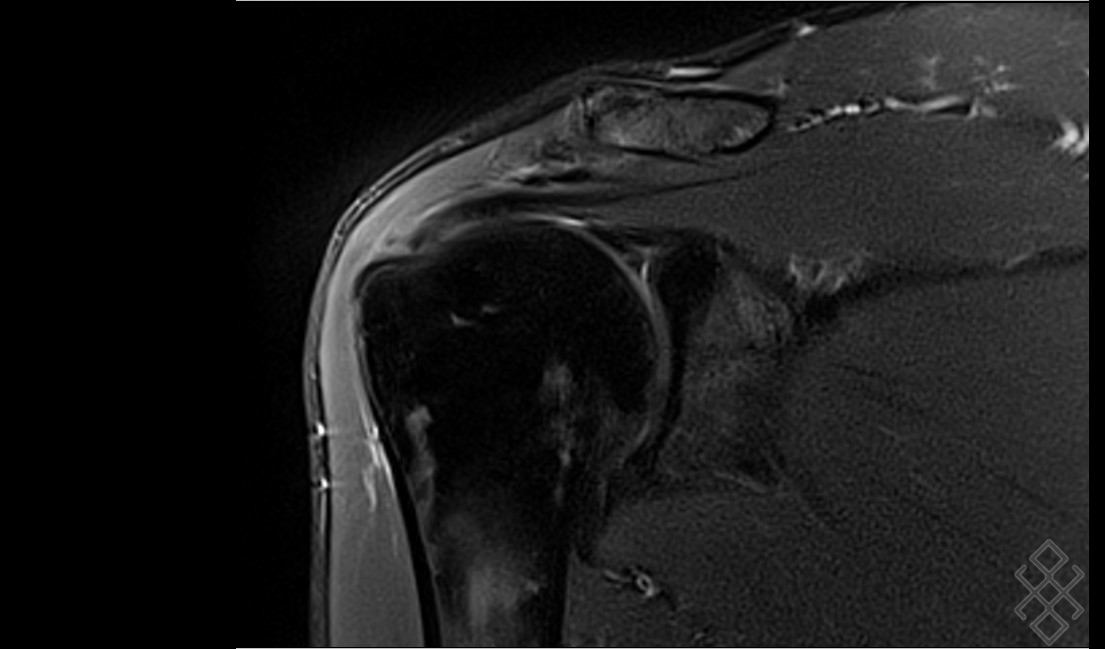

L'examen irm de l'épaule est utilisé pour un traumatisme, des lésions tendineuses présumées, une tendinose, une rupture, une calcification, des lésions de la coiffe des rotateurs et analogues.

Mais pour étudier l'articulation de l'épaule, la technique la plus sûre et la plus informative est l'imagerie par résonance magnétique (irm).

L’épaule sera entouré d’une antenne souple ou d’une coque plus dure (suivant les constructeurs).

L’épaule à examiner doit être le plus au centre de la table possible :